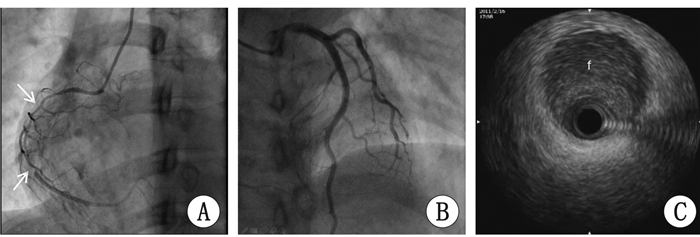

1 资料与方法病例1 患者,女,42岁,因“右冠支架植入术后5年余,再发胸痛1周”于2016年9月16日入院。2011年2月11日曾因“反复胸痛半月,晕厥2次”住本院。2011年1月26日因丧父悲痛后反复胸痛伴晕厥,当地卫生院予以输液时再发晕厥后转本院。入院后查心电图示:Ⅱ、Ⅲ、aVF导联T波倒置,胸主动脉CTA未见异常。2011年2月16日冠脉造影显示右冠开口、近段及中段弥漫性狭窄病变,右冠中段最重处近乎闭塞(图 1A、B)。右冠IVUS显示右冠近段及中段夹层,血肿延伸至右冠开口(图 1C)。诊断:自发性右冠冠状动脉夹层,急性非ST抬高性心肌梗死。行右冠植入4枚紫杉醇药物支架。术后服用拜阿司匹林、氯吡格雷、美托洛尔等药物,无再发胸痛。2016年9月8日无诱因下出现反复胸骨中上段胸痛,放射至左侧肩背部,每次持续20 min后自行缓解。入院查体:BP113/60 mmHg(1 mmHg=0.133kPa),神清,两肺呼吸音粗,心率80次/min,律齐。心肌酶:CK-MB 34 U/L(参考值2~25),肌钙蛋白I(TNI)3.115 pg/mL(参考值0.000~0.060)。心电图:Ⅱ、Ⅲ、aVF、V1~V6导联T波双向或倒置。诊断为:急性非ST抬高性心肌梗死,自发性右冠冠状动脉夹层,右冠支架植入术后。冠脉造影显示:左前降支中段至远段弥漫性狭窄最重80%狭窄,对角支开口75%狭窄,左回旋支开口70%狭窄,右冠开口原支架内70%狭窄(图 2A、B、C)。IVUS显示:右冠开口最小管腔面积2.91 mm2,左主干至左前降支远段全程夹层及壁内血肿形成,远段管腔重度狭窄,左回旋支开口重度狭窄、未见夹层及血肿(图 2D、E、F)。以紫杉醇药物球囊行右冠开口原支架内扩张术。继续予以抗血小板、扩冠等药物治疗,出院随访至今,无不适主诉。

| 图 1 病例1冠脉造影及右冠IVUS(2011年2月16日):白色箭头示右冠自发性夹层,f示假腔; |